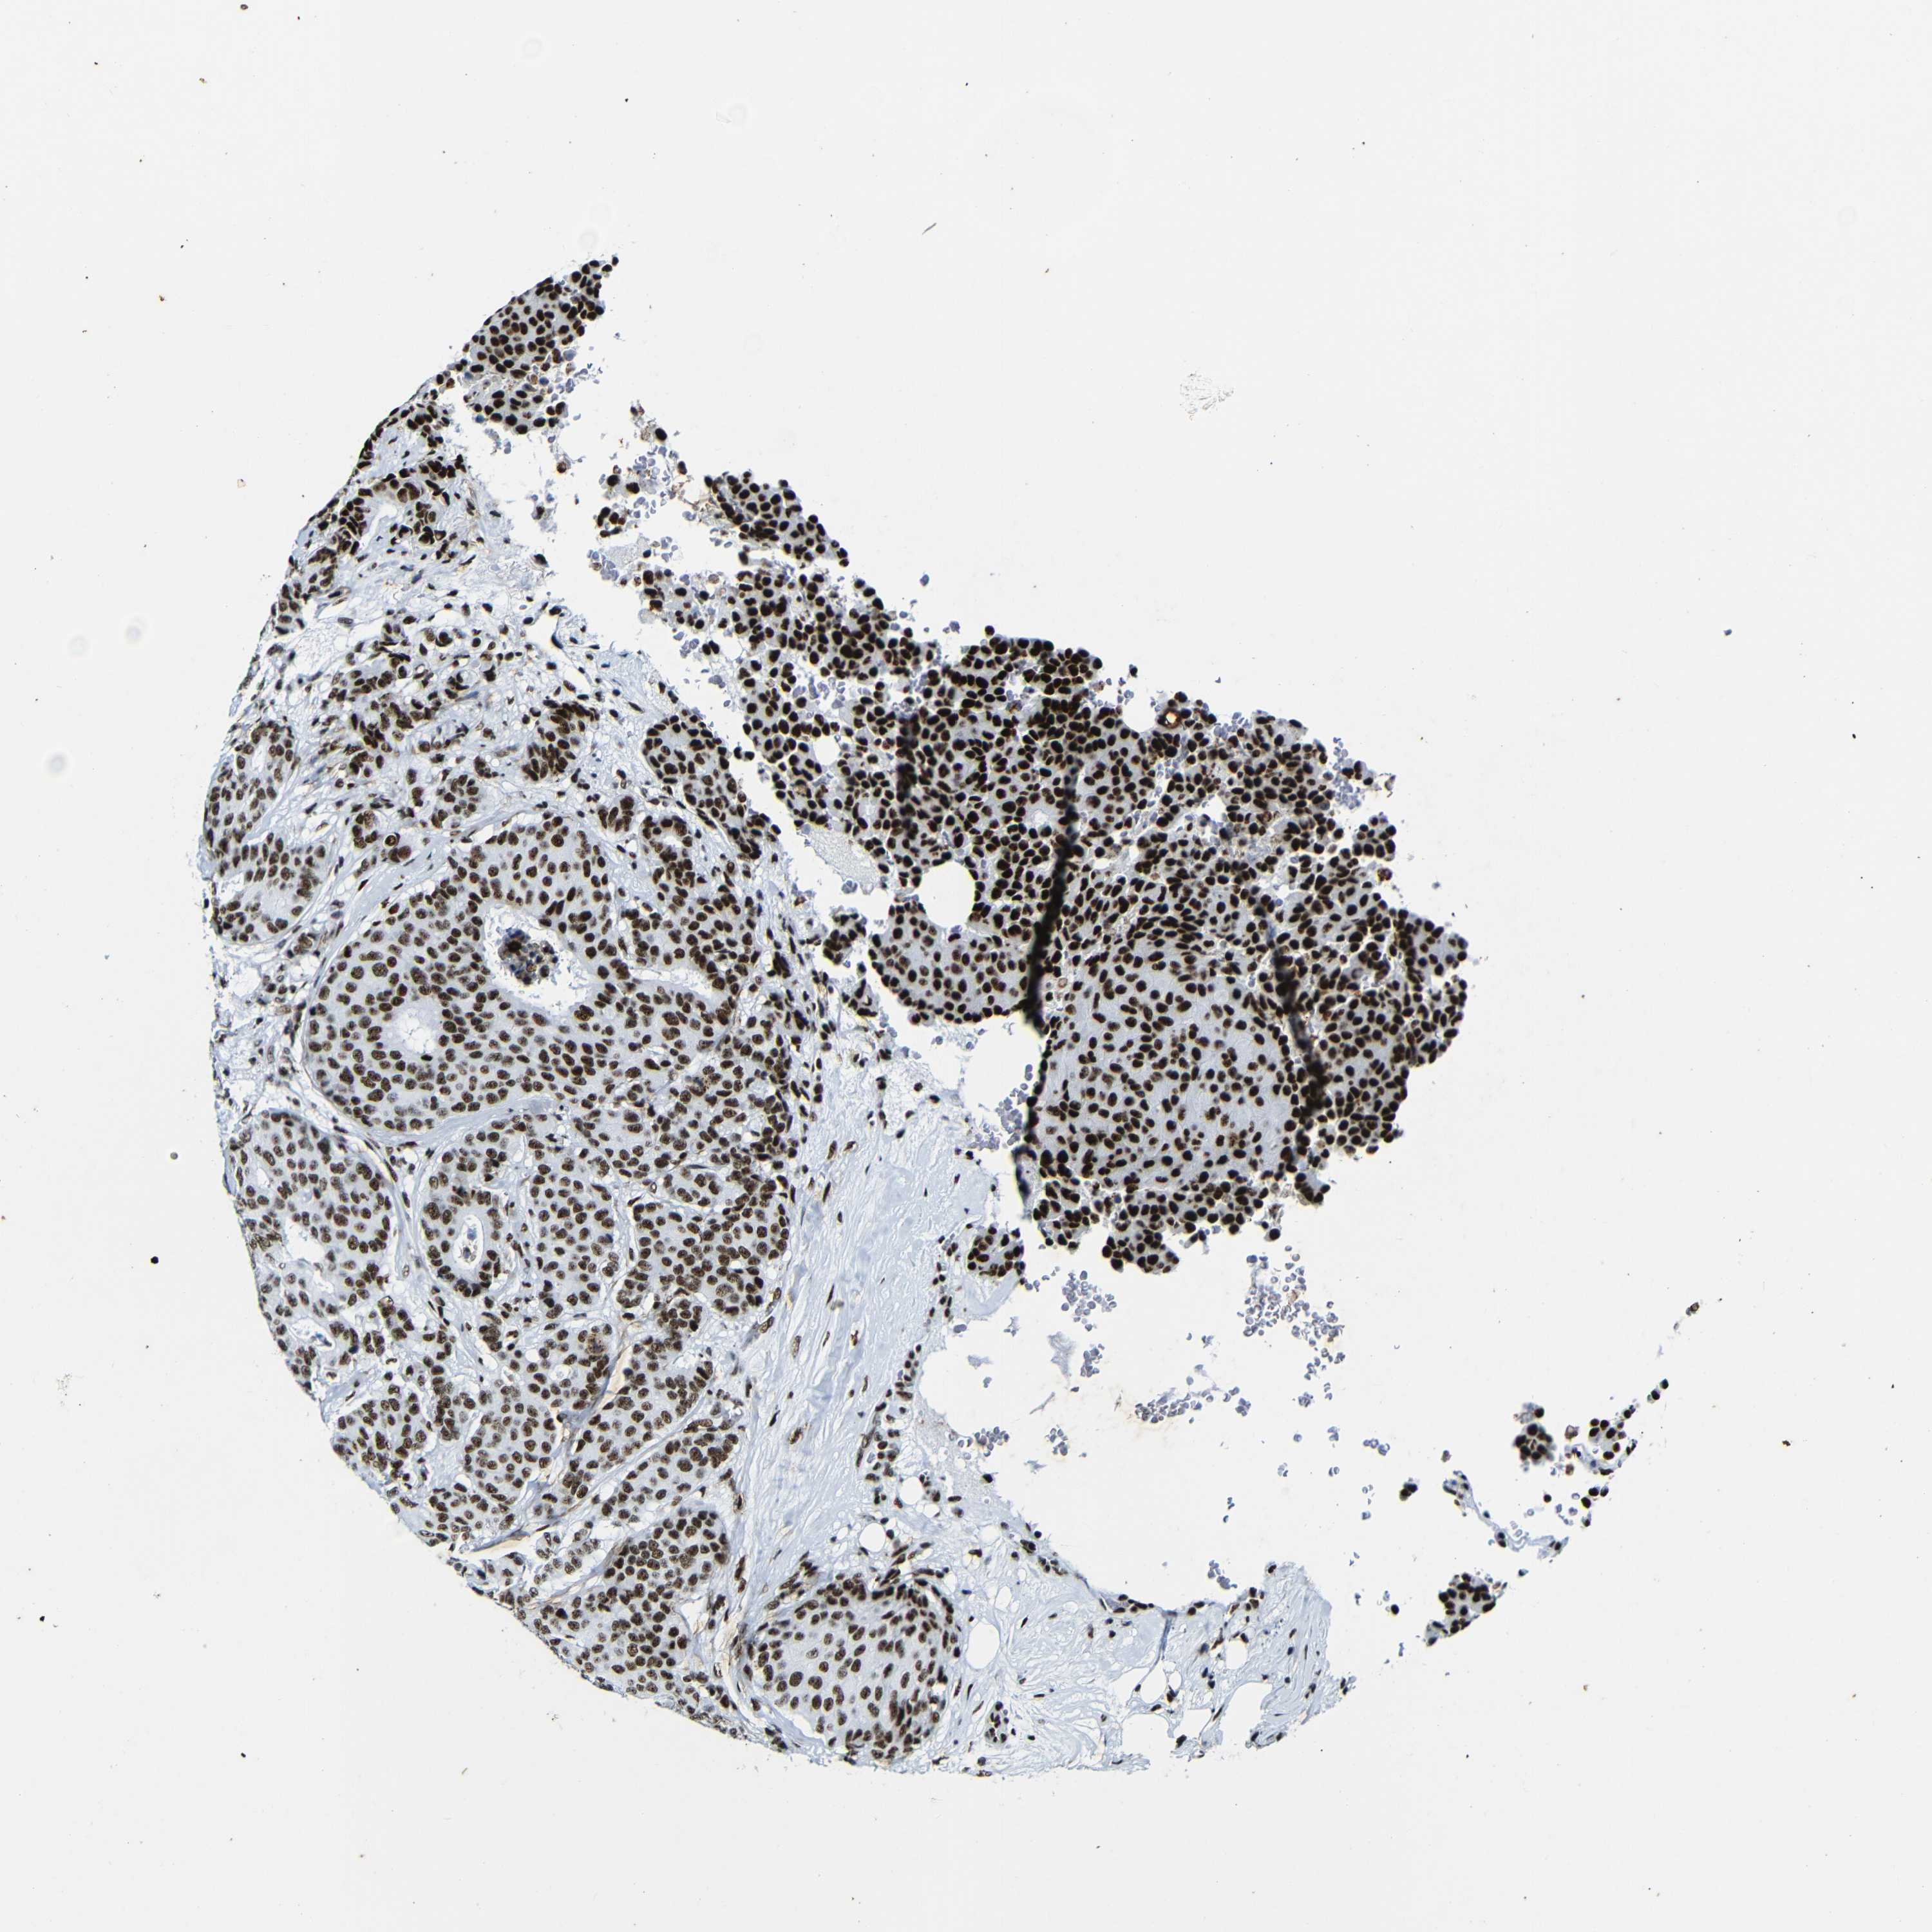

CANCER BREAST CANCER Show tissue menu

BRCA TCGA BRCA VALIDATION PROTEIN EXPRESSION